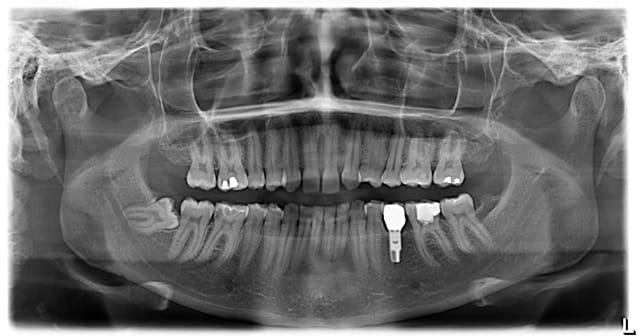

37 semble aussi abrasée, donc je soupconne une abrasion et des parafonctions

couronne CAO

Je ne vois pas en quoi l'usure provoquée de 36 et l'usure soupçonnée sur 37 seraient des contre-indications . Tant qu'à avoir peur , l'implant lui même avec un problème occlusal général et des dysfonctions...ouin .

Peut-être la cause de la perte de la 35 , (mais c'est probablement une agénésie) pourrait donner une réponse et orienter le choix de protection totale et le choix invasif d'emblée de la 36 . Je trouve étonnant que l'espace (35) soit intact , tu nous diras si tu as fait de l'ortho pour regagner l'espace et l'historique du secteur 3 .

Mais il y a fort à parier au regard de la courbure importante de la racine mésiale qu'il faudra élargir cette chambre en mésiale, à ceci s'ajoute une carie débutante toujours en mésiale (sans parler des caries multiples un peu partout), donc on se dirige à mon avis vers de la prothèse périphérique.

Par contre le titre dit "bio et ensuite", ben ensuite, c'est soins conservateur multiples (y a du boulot), motivation hygiène (c'est bizarre toutes ces caries dans une bouche présentant un implant, signe de patient généralement motivé!), et enfin CCC.

patiente 26 ans,

effectivement implant 35 suite à la perte de la 75 tardivement ( agénésie de la 35 )